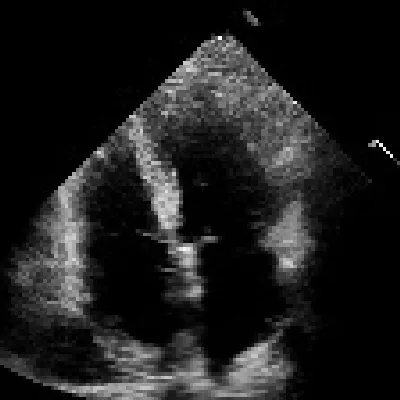

EchoFlow

a4c_decoded.png